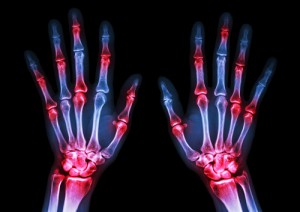

I ricercatori hanno condotto uno studio su pazienti anziani con diagnosi di artrite reumatoide che si erano sottoposti ai cosiddetti multibiomarker disease activity test (MBDA), che valutano l’attività della malattia attraverso esami del sangue. Dai dati raccolti per Medicare, la compagnia di assicurazione con la quale gli anziani erano assicurati, Muntner e colleghi hanno esaminato i casi di ricovero in ospedale per eventi quali infezioni gravi, come polmoniti o sepsi, infarto e malattie coronariche. I punteggi dei test MBDA, invece, che variavano da 1 a 100, rientravano nei dati Medicare. In totale, i ricercatori hanno analizzato i dati provenienti da 17.433 e 16.796 pazienti che avevano avuto, rispettivamente, infezioni o ictus e malattie coronariche. L’età media era di 69 anni e più della metà, il 79%, erano donne. I ricercatori avrebbero invece escluso i pazienti con artrite psoriasica, lupus eritematoso sistemico, malattia infiammatoria intestinale, gran parte dei tumori maligni e altre malattie correlate, nonché coloro che, per qualsiasi motivo, avevano assunto farmaci anti-TNF, sia biologici che sintetici, o farmaci modificanti la malattia.

Dai risultati sarebbe prima di tutto emerso che i pazienti con i punteggi più bassi di MBDA tendevano ad essere mediamente più giovani, avevano meno comorbidità e usavano meno corticosteroidi, ma più farmaci biologici. In totale, durante il follow-up, si sarebbero verificati 452 casi di infezione, 132 infarti e 181 eventi coronarici. Punteggi MBDA più alti sarebbero stati significativamente associati a infezioni, mentre un’attività dell’artrite reumatoide maggiore sarebbe stata anche collegata a più infarti e malattie coronariche. “Questo studio sottolinea l’importanza del controllo della malattia per ridurre gli attacchi di cuore e le infezioni”, spiega Eric Matteson, della Mayo Clinic di Rochester, in Minnesota, che non era coinvolto nello studio. “Questi sono tra i dati migliori tra tutti quelli disponibili che suggeriscono un collegamento tra artrite reumatoide e malattie cardiache”, sottolinea Jonathan Graf, dell’Università della California di San Francisco, anche lui non coinvolto nello studio. “Penso che questi risultati dimostrino che l’infiammazione è una possibile causa di malattie cardiache”, sottolinea l’esperto, che ha anche precisato che “dovremmo trattare i pazienti nel modo più aggressivo possibile”.